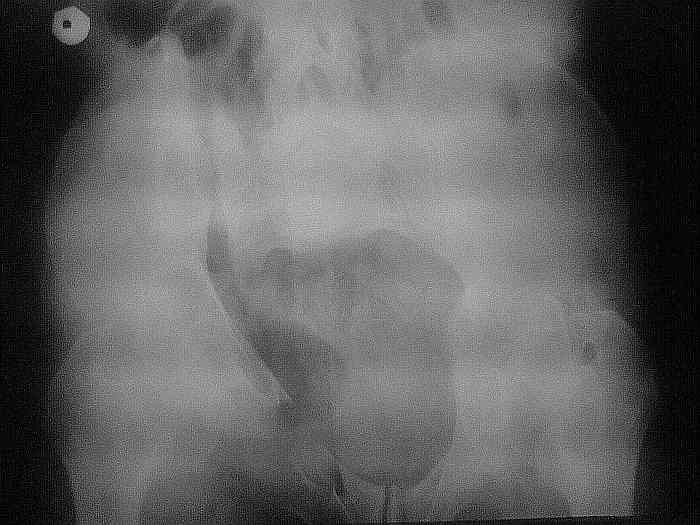

Остается только вариант закрытого аппаратного лечения. В аттаче положение отломков на вытяжении в прямой (АР) проекции. Для сравнения снимок до и во время вытяжения.

> Остается только вариант закрытого аппаратного лечения.. В аттаче

> положение отломков на вытяжении в прямой (АР) проекции. Для сравнения

> снимок до и во время вытяжения.

Первоочередно для тазовых операций важно обследование, снимки таза в инлет, оутлет и прямая

проекция.

На сравнительном снимке правый полутаз опустился

недостаточно, можно добавить вес и сделать все стандартные снимки.